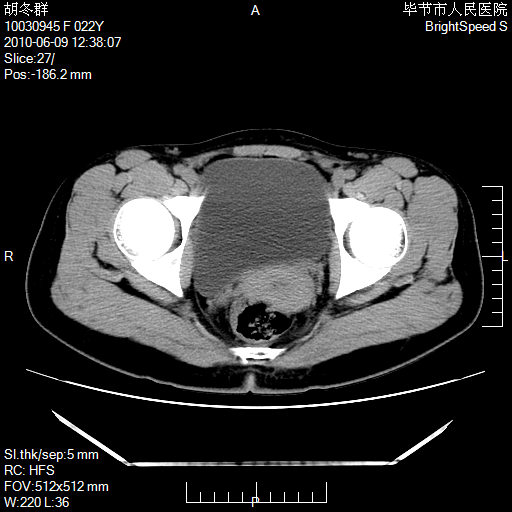

患者23岁,发现腹部包块3月。

我当时考虑重复膀胱,但我错得很厉害,我不明白,囊肿排尿后为什么能到膀胱位置。

囊性病变,可以增强检查,不除外输尿管囊肿

盆腔内囊性占位性病变;考虑左侧卵巢囊腺瘤。

有分隔、壁薄,支持考虑左侧卵巢囊腺瘤。

左侧卵巢浆液性囊腺瘤。

有分隔、壁薄,支持考虑左侧卵巢囊腺瘤。排尿后,膀胱缩小,由于重力作用,肿块下移就到了膀胱位置,很好理解。